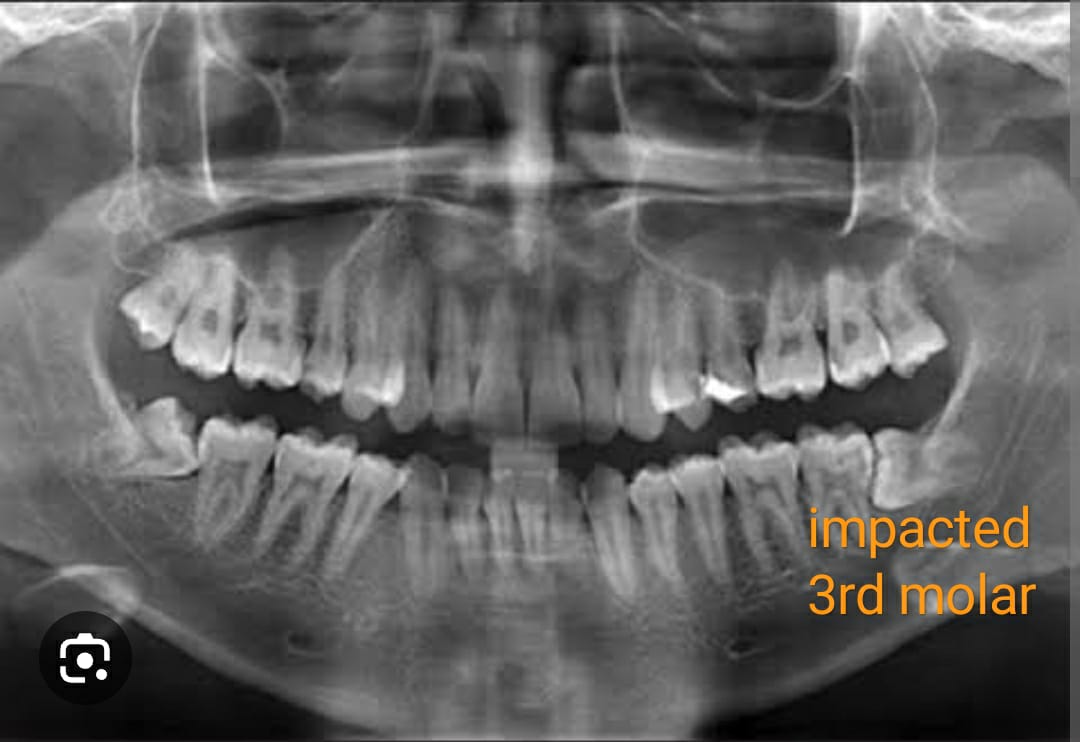

During her consultation, Priya met with Dr. Anjali, a compassionate and experienced dentist who understood the nuances of Priya's situation. Dr. Anjali explained the procedure in detail, addressing Priya's concerns and fears with patience and empathy. Priya learned that her wisdom teeth were not only causing pain but also posing a risk of infection and misalignment, which could lead to more severe dental issues in the future.

In a country like India, where dental health often takes a back seat to other priorities, Priya's story serves as a reminder of the importance of addressing dental issues promptly. Wisdom teeth extraction is not merely a medical procedure; it's a gateway to a healthier, happier life.